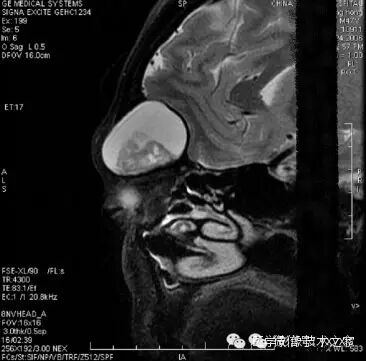

铁磁性物质具有很大的磁化率,可能导致明显的磁场变形。

不同的序列,金属伪影大小不同。FSE< GRE< EPI

图像变形。或明显异常高/低/混杂信号在不同层面上伪影位置往往改变--“会走动的伪影”